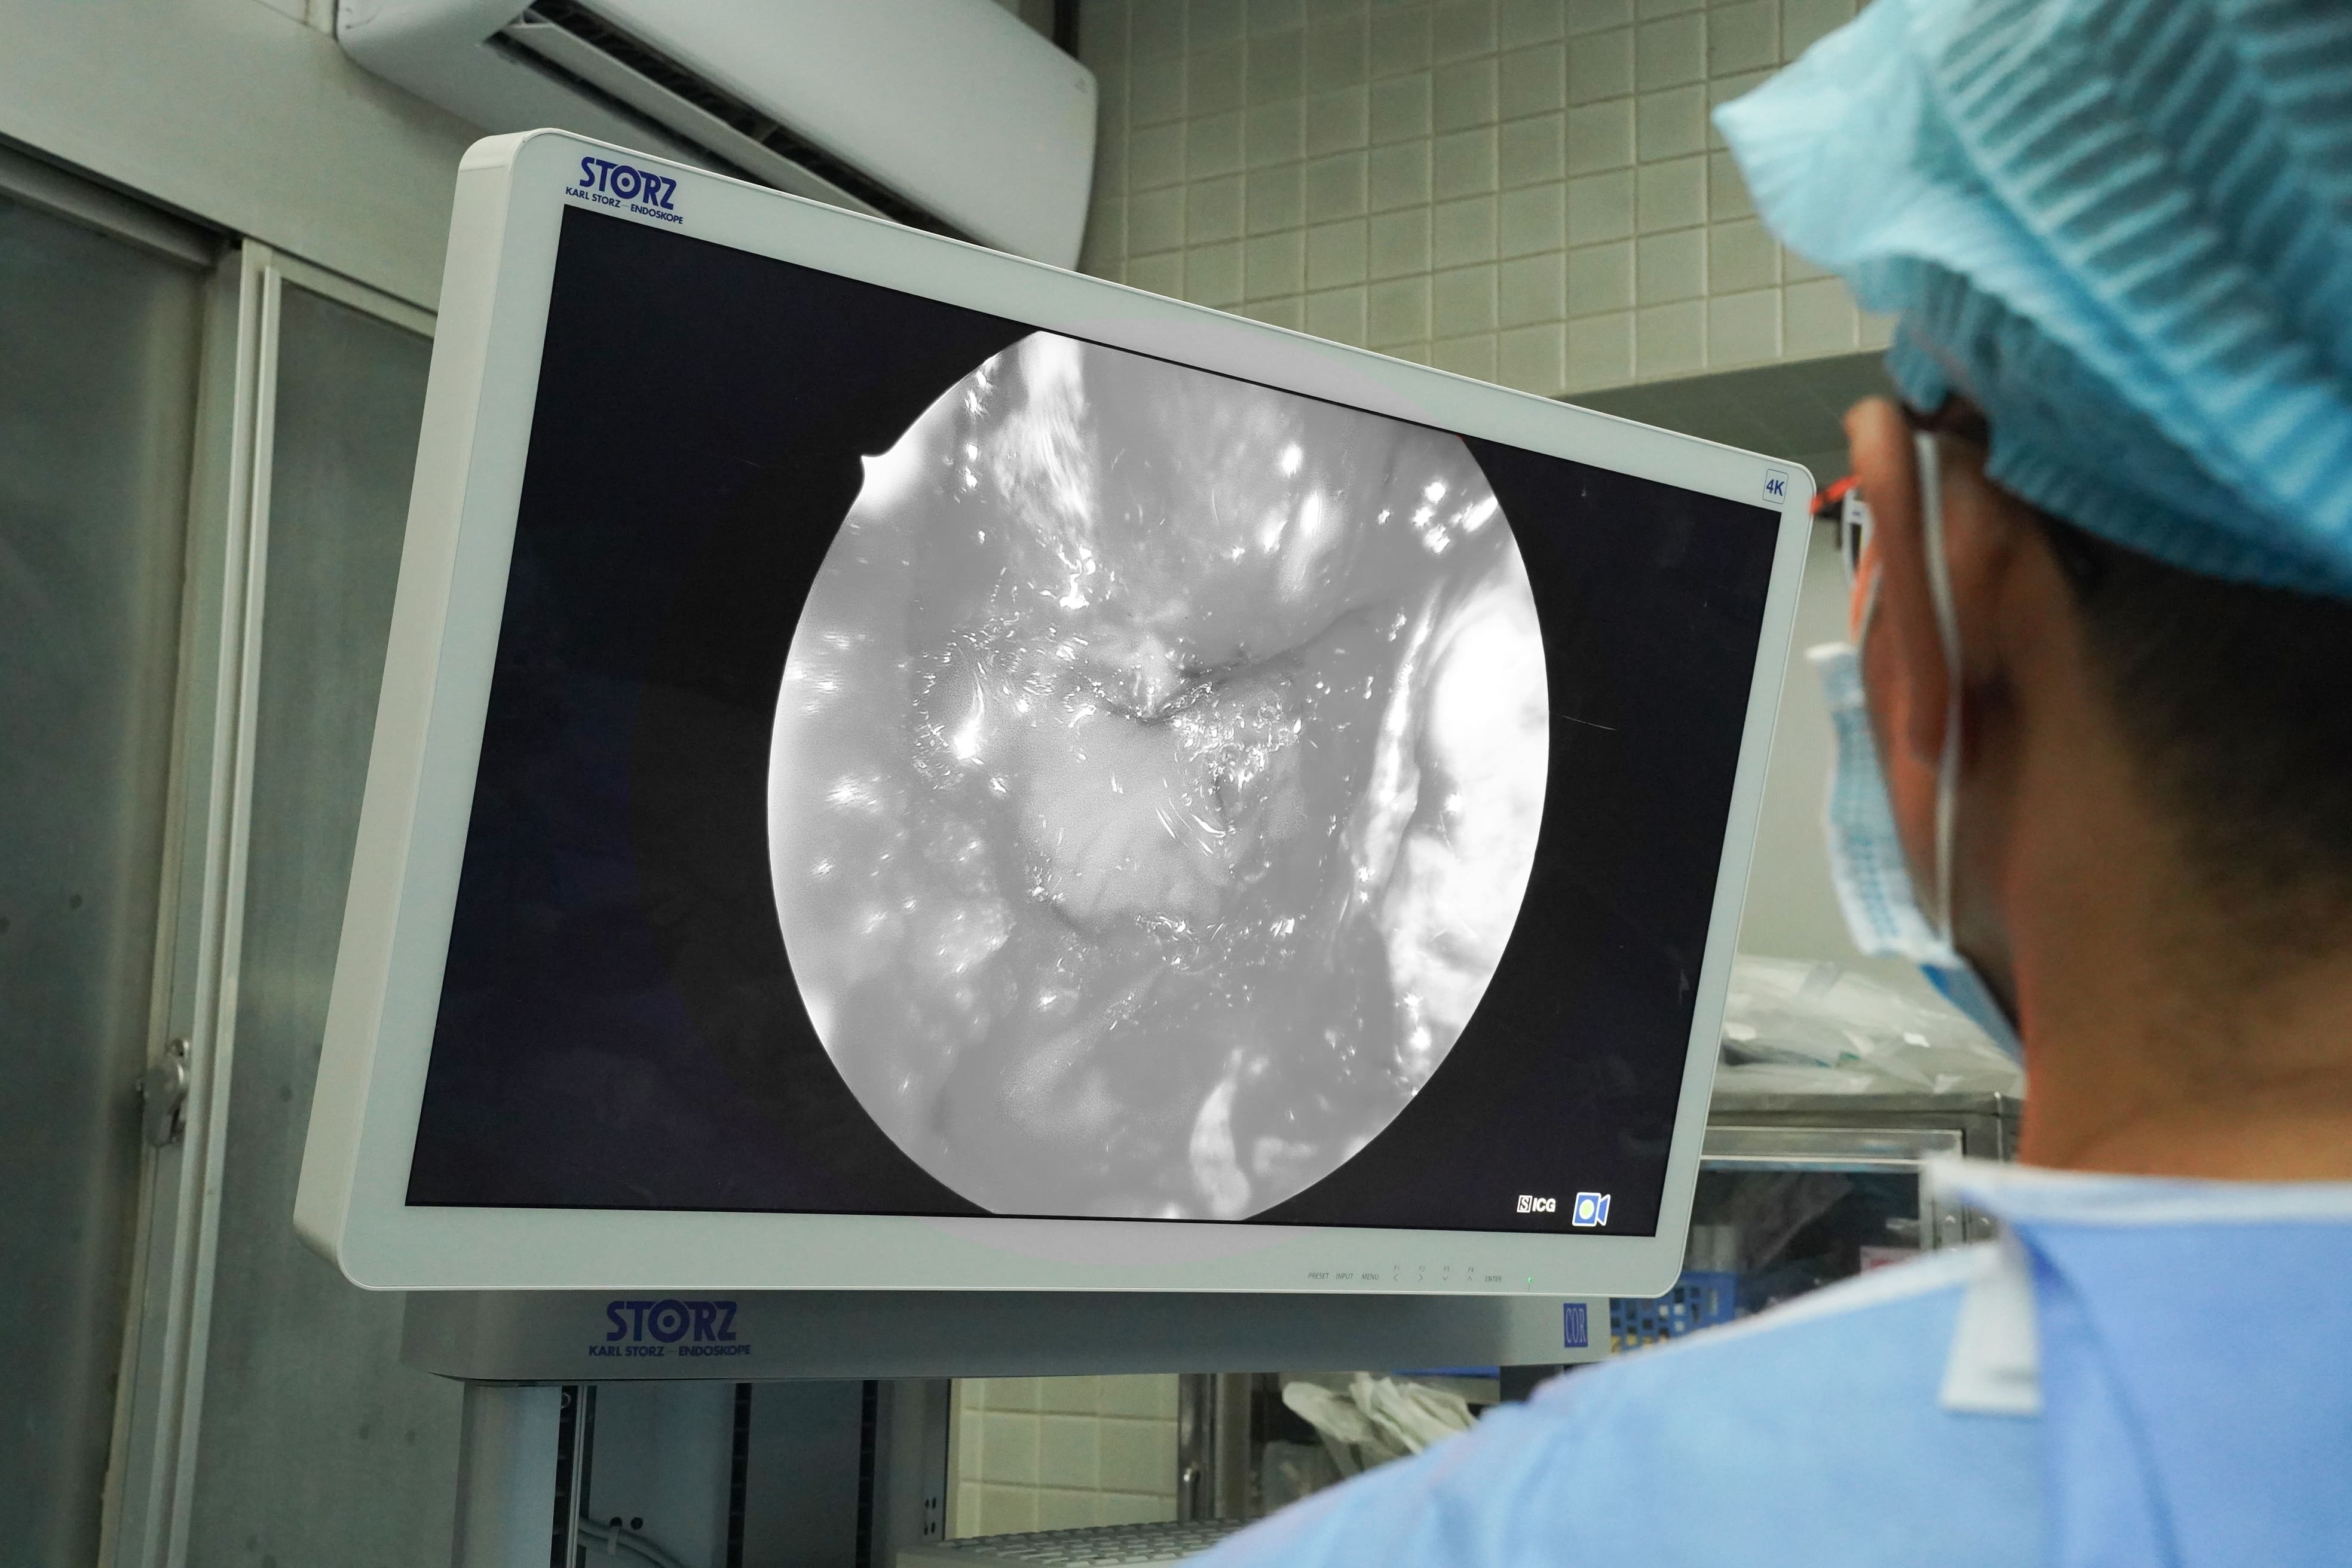

Trước tình trạng của bệnh nhân, ê-kíp điều trị quyết định phẫu thuật nội soi qua đường mũi - xoang bướm. Điểm đặc biệt là ê-kíp đã sử dụng Hệ thống phẫu thuật nội soi Thần kinh 4K - ICG, công nghệ hiện đại mà Chợ Rẫy là cơ sở y tế đầu tiên tại Việt Nam ứng dụng từ giữa năm 2025.

Hệ thống phẫu thuật nội soi Thần kinh 4K - ICG mở ra cơ hội điều trị cho các bệnh lý thần kinh phức tạp. Ảnh: BVCC. |

Phân tích về ưu điểm của hệ thống này, TS.BS Trần Thiện Khiêm, khoa Ngoại thần kinh, người trực tiếp phẫu thuật, cho biết với u khổng lồ, yêu cầu quan trọng nhất là lấy tối đa khối u nhưng vẫn bảo tồn cuống tuyến yên, tuyến yên lành và hệ thống mạch máu - thần kinh lân cận, đặc biệt là hai động mạch cảnh trong.

Với kỹ thuật mới này, khi tiêm thuốc huỳnh quang ICG, mạch máu và các cấu trúc quan trọng sẽ hiện rõ trên màn hình 4K, giúp phẫu thuật viên nhận diện tốt hơn, từ đó thao tác chính xác hơn. Nhờ hệ thống này, ê-kíp đã lấy được gần như toàn bộ khối u, nâng cao hiệu quả phẫu thuật và chất lượng điều trị.